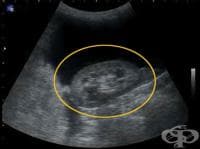

АКЦЕНТИ ОТ РУБРИКА УЛТРАЗВУКОВО ИЗСЛЕДВАНЕ (ЕХОГРАФИЯ)

АКТУАЛНО ОТ РУБРИКА УЛТРАЗВУКОВО ИЗСЛЕДВАНЕ (ЕХОГРАФИЯ)